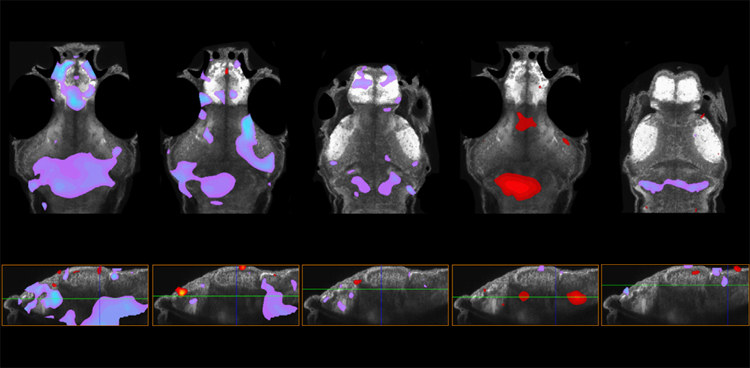

在五種具有自閉癥相關(guān)基因變異的斑馬魚模型中,前腦的大小增加(紫色)或減少(紅色)。

圖1 在五種具有自閉癥相關(guān)基因變異的斑馬魚模型中,前腦的大小增加(紫色)或減少(紅色)。